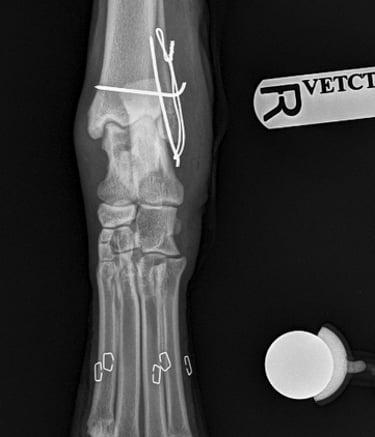

Orthogonal xrays reveal a lateral malleolus fracture (Fig.1 and 2), stress views and palpation revealed stable joint with no affection of collateral ligaments but due to the fracture there is some degree of rotational instability. Surgical stabilization is strongly advised as Buddy is a 40 kg patient.

Fig. 2

Fig. 1